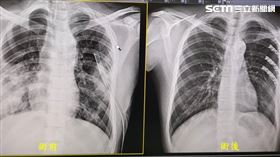

胸骨折挫傷肺 鈦金屬肋骨手術救一命

隨著重型機車的風潮興起,國人愛好重機的人口比例也日漸...